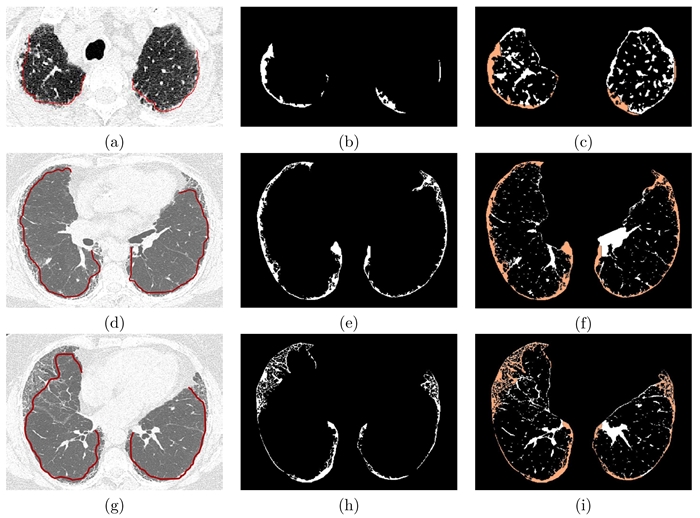

Las regiones seleccionadas por el médico como regiones con presencia de fibrosis se compararon en términos del %F P con los resultados obtenidos a través del método basado en la segmentación con el algoritmo de CV. Esta comparación se realizó para cada una de las 5 rebanadas de TAC seleccionadas por cada paciente. La Figura 5 muestra particularmente 3 casos, donde se indican las regiones definidas por el médico y las regiones obtenidas por el método propuesto. En la Figura 5 se presenta en la primer columna, las imágenes originales con la región correspondiente a fibrosis, delimitada por el médico mediante una línea roja; en la segunda columna, las regiones de fibrosis obtenidas a partir del método propuesto y la última columna muestra las imágenes de diferencia traslapadas con las regiones de fibrosis mostradas en la segunda columna, indicadas en color naranja. Si se comparan visualmente las regiones seleccionadas por el médico y las obtenidas por el método semi-automático se puede observar que ambas regiones son muy semejantes.

Figura 5 Comparación de regiones con presencia de fibrosis obtenidas por el médico y por el método propuesto. Imagen original de una rebanada con el área de fibrosis delimitada por el médico mediante una linea roja (a,d,g), regiones de fibrosis utilizadas para el calculo del %F P mediante el método propuesto (b,e,h), imágenes de diferencia traslapadas con la región de fibrosis obtenida a través del método semi-automático indicada en color naranja (c,f,i).

La Tabla 1 muestra los porcentajes de fibrosis estimados en cada rebanada y en cada pulmón obtenidos por el método propuesto basado en el algoritmo CV, y los valores estimados por el médico experto. Los porcentajes obtenidos entre el método semi-automático y el experto clínico difieren en gran parte de las rebanadas de ambos pacientes. Sin embargo, es importante mencionar que en la mayoría de rebanadas coincide la proporción de un área mayor o menor afectada por fibrosis entre pulmón derecho e izquierdo, entre el experto y el método semi-automático. En particular, se logró una aproximación muy cercana en el caso de la rebanada 3 del paciente 1, este caso se muestra en la Figura 5 (a,b,c). La diferencia entre porcentajes estimados puede ser debida principalmente a la estimación subjetiva del %F P por parte del experto clínico, ya que en la Figura 5 se puede apreciar que las regiones obtenidas por el médico y por el método propuesto son muy similares, sin embargo los porcentajes asignados por el experto clínico difieren del área calculada con base a la información presente en la imagen. Por ejemplo, para la rebanada 22 del paciente 2 mostrada en la Figura 5 (d,e,f), el experto clínico asignó un %F P de 30 % y 20 % para pulmón derecho e izquierdo respectivamente y los %F P obtenidos por el método semi-automático fueron 10.9 % y 8 % respectivamente, pero visualmente se puede observar que las regiones seleccionadas por el experto y por el método propuesto poseen una gran coincidencia. En el tercer caso, que corresponde a la rebanada 26 del paciente 2, mostrado en la Figura 5 (g,h,i), el experto encontró un %F P de 40 % y 20 % para pulmón derecho e izquierdo respectivamente, mientras que el método semi-automático determino un %F P de 9.9 % y 6.4 % respectivamente. Estos resultados entre estrategias de aproximación de áreas afectadas por fibrosis tienen una diferencia mucho mayor, esta gran diferencia podría reducirse si para el cálculo del %F P se consideran todos los pixeles dentro de la ROI que define la zona afectada por inflamación y fibrosis.